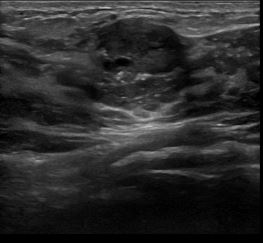

상기환자는 외부검사 이상소견으로 내원하신 30대중반 여성분으로 의심스러운 좌측혹

조직검사 시행해 유방암으로 진단되었습니다